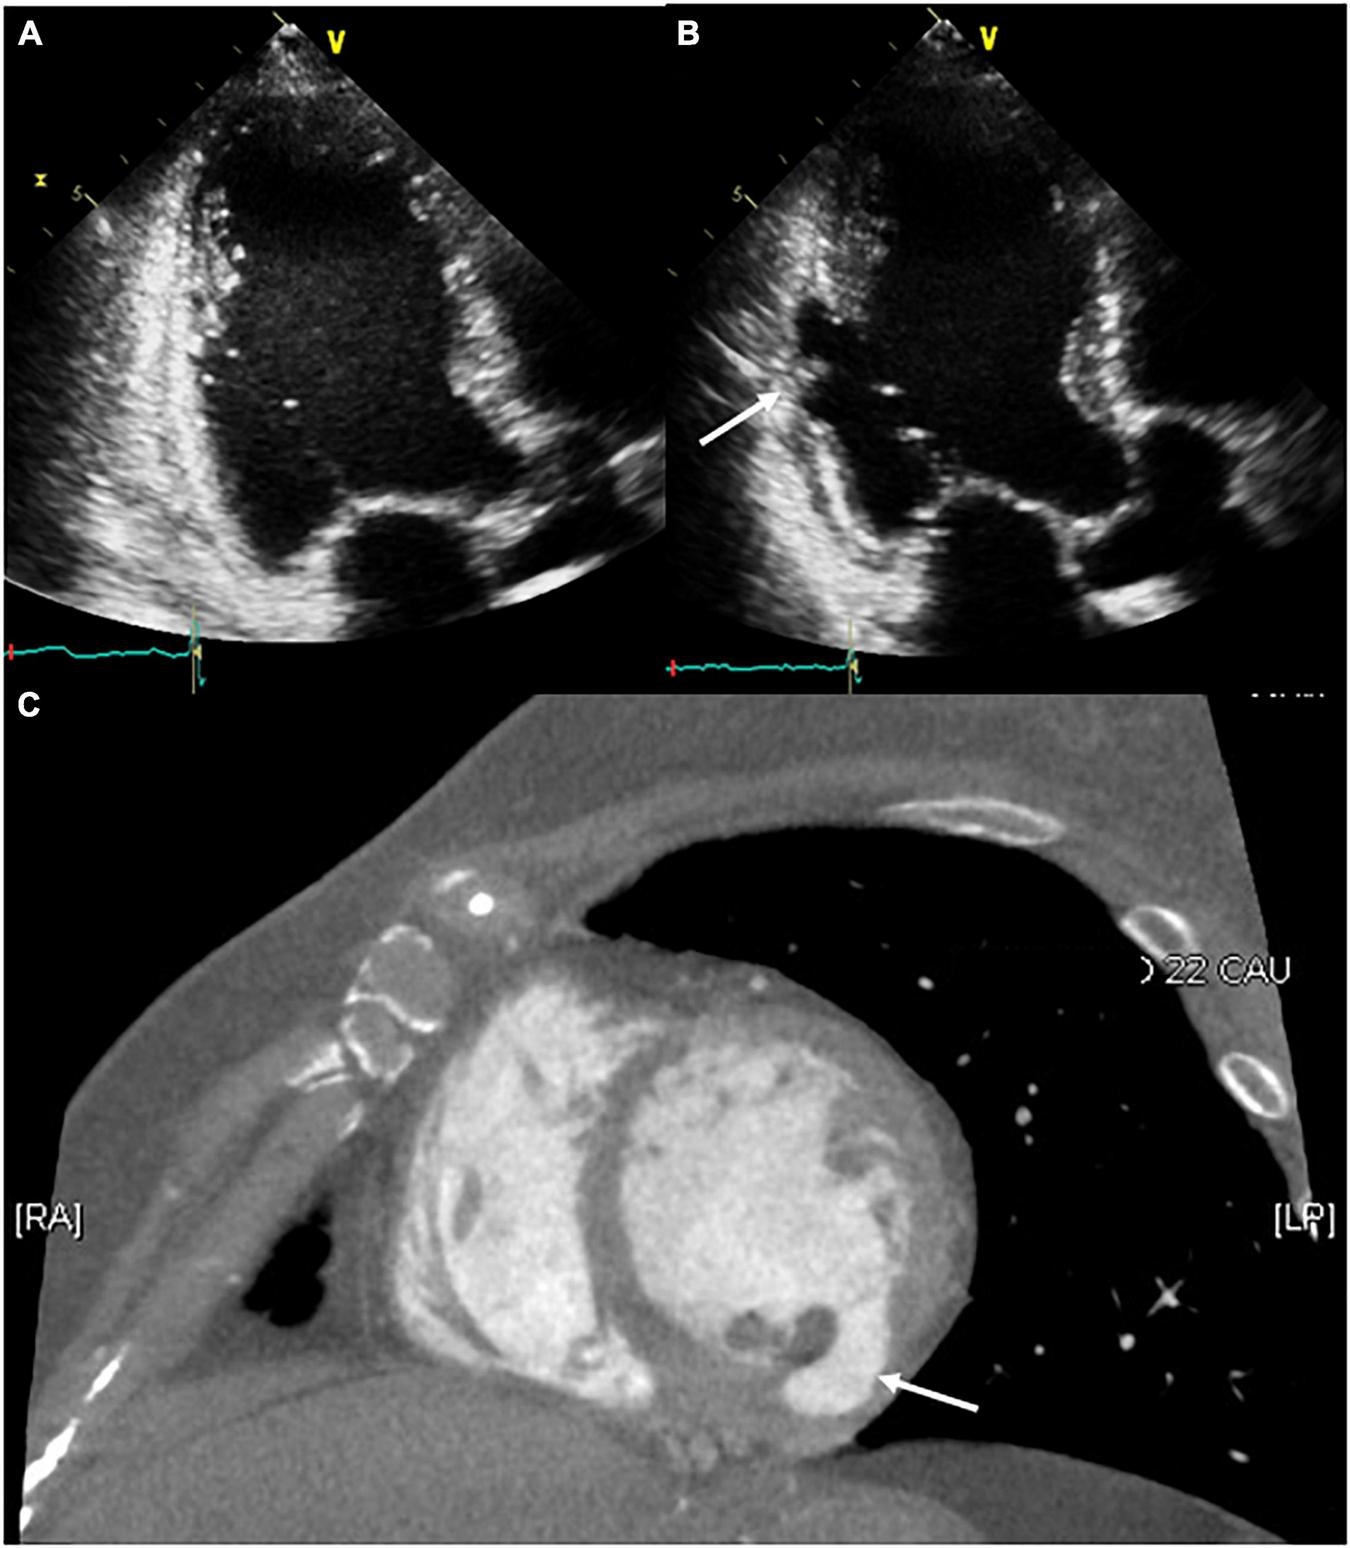

FIGURE 3

Serial follow-up of the ablation site using transthoracic echocardiography. (A) The day after the procedure, no structural changes around the ablation site were observed. (B,C) After 2 months of follow-up, the development of a pseudoaneurysm on the ablation site (white arrow) was confirmed through transthoracic echocardiography and contrast-enhanced computed tomography.

After 2 months of follow-up, the patient remained free of VT. Echocardiography showed improved LV systolic function with LV ejection fraction of 50% and a decreased LV size with LV end-diastolic dimension of 52 mm, but a pseudoaneurysm (26 × 9 mm) that has the ratio of the maximum diameter of the orifice to the maximum internal diameter of the cavity was lesser than 0.50 was identified at the base of the LV posteromedial papillary muscle where a steam pop had occurred without pericardial effusion (Figure 3B and Supplementary Video 2). The patient was asymptomatic; therefore, she was referred to the outpatient clinic for observational follow-up during the following year without anticoagulation or antiplatelet agents; the patient underwent no further interventions. One year later, cardiac CT revealed that the pseudoaneurysm that typically has a neck narrower than the diameter of the aneurysm remained present but showed no signs of a size change or other complications such as thrombus formation (Figure 3C).

In the case reported here, although the presence of turbulent flow by pulsed Doppler was unclear, other echocardiography and CT findings suggested a pseudoaneurysm. Most plausible cause of the pseudoaneurysm was an inaudible steam pop that occurred during the ablation. A steam pop occurs by the myocardial explosion when the tissue temperature reaches 100°C high enough to cause tissue vaporization and gas production; by ICE visualization, it appears as a sudden hyperechogenic intramyocardial microbubble formation around the catheter. It is a potentially life-threatening complication of radiofrequency ablation because it can cause structural defects (10). Intraprocedural ICE and transthoracic echocardiogram 1 day after the procedure revealed no tissue defects around the ablation site and no pericardial effusion. However, echocardiography performed at 2 months of follow-up confirmed the delayed development of a pseudoaneurysm at the first ablation site. We speculated that an inaudible steam pop cause both acute denuding and delayed endocardial necrosis. Here we reported a rare case of delayed LV pseudoaneurysm confirmed by echocardiography and cardiac CT that developed on an inaudible steam pop site occurring during ablation for the treatment of VT originating from the papillary muscle of the LV. However, magnetic resonance imaging is thought to be more useful when considering the diagnosis and follow-up of structural defects such as pseudoaneurysm. Serial imaging-based follow-up can facilitate the identification of pseudoaneurysms with delayed development, even when intraprocedural and short-term imaging-based follow-up confirms no procedure-related complications.